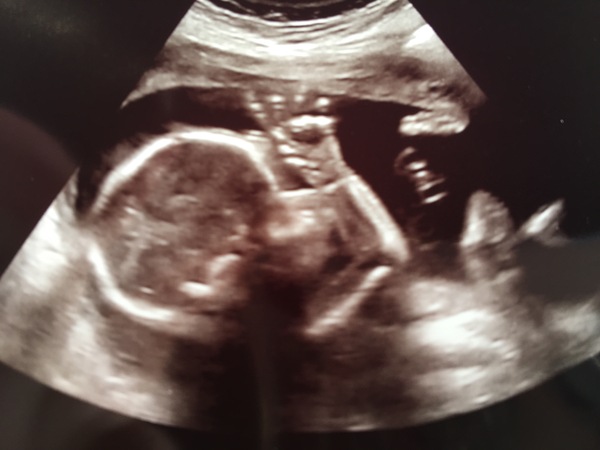

Dixie congratulations on a lovely looking scan! Grin

Great scan Dixie! Well done on sticking to team vanilla, I'm far too impatient for that!

Dixie lovely scan pic and well done for staying team vanilla!

Team 💙 by the way. Baby says hello ☺️

starmist I'm so sorry that you're having to go through this. I've replied to you on the FB group too. While you're waiting for your next scan I would focus on your extremely low risk blood results (for comparison mine were 1 in 15,000 when combined with a good NT measurement so 1 in 98,000 for just blood work is great!). If it were me I would also be working through the various outcomes with my DH and thinking about what action we would take in each situation, for example my DH and I decided that if we found out that our baby was at high risk of DS we wouldn't do anything differently so there would be no point in us doing further (invasive) testing. That stuff is so personal though so worth giving it a bit of thought. Your scan pic is beautiful and congratulations on being our first official team blue! Smile